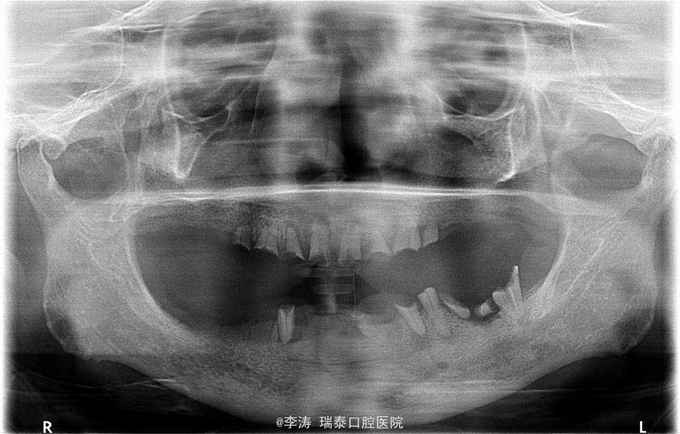

患者要求修复缺失牙

全口大部分牙缺失,上頜4~4残根,下颌32,34,34,36,37,43残根。大部分残根根尖暗影明显。除24,36,43松动III度外其余牙根均不松动

建议将松动牙根拔除,其余考虑根管治疗,尝试进行保留,然后覆盖义齿修复。

对于覆盖义齿下面的残根,多长的残根有保留价值?多大的暗影应该拔除,书上都没有明确的标准,所以想问一下各位,想14这么短的牙根的保留价值如何,还是该直接拔掉?它现在一点都不松动?